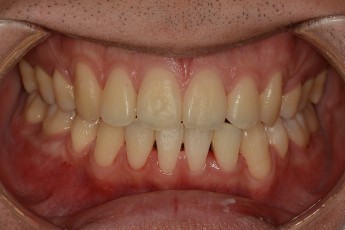

- 덧니교정

Before

After